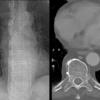

Paraspinal lines

Date: 10/23/2010

Views: 3267

Views: 3138